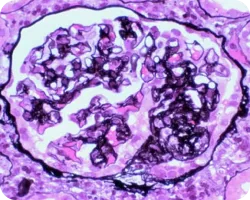

Клеточные или фиброзно-клеточные полулуния

Image

Наличие клеточных или фиброзно-клеточных полулуний (С1) характеризует значимо более высокий риск неблагоприятного почечного исхода при отсутствии иммуносупрессивной терапии, однако исчезающий при ее проведении. Обнаружение же С2-признаков говорит о неблагоприятном почечном исходе вне зависимости от иммуносупрессии22.